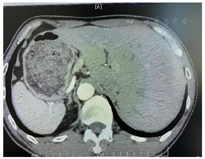

相关检查:血常规、肝肾功、血脂、血糖、尿蛋白及微量白蛋白、胸片、皮质醇节律、血浆甲氧基肾上腺素类物质未见异常。电解质:K 2.03mmol/L。心电图:窦性心律;ST-T改变(图1)。心脏彩超:左房稍增大(前后径35 mm)(图2)。动态血压监测:白天平均血压134/88 mmHg,夜间平均血压134/83 mmHg,全天平均血压134/86 mmHg。高血压五项(立位):血管紧张素活性1.99 uIU/ml/h,醛固酮539.00 pg/ml,血管紧张素Ⅱ 11.40 pg/ml,皮质醇326.00ng/ml,促肾上腺皮质激素36.30 pg/ml。高血压五项(卧位):血管紧张素活性<0.5 uIU/ml/h,醛固酮634.00 pg/ml,血管紧张素Ⅱ<5 pg/ml,皮质醇233.00 ng/ml,促肾上腺皮质激素37.10 pg/ml。肾上腺CT(增强):左侧肾上腺体部小结节,考虑小腺瘤,请结合临床及其他检查(图3)。双侧肾上腺静脉采血:左侧肾上腺静脉两次采血结果分别为:①醛固酮40 150 pg/ml,皮质醇3 750ng/ml,醛固酮/皮质醇10.7;②醛固酮14 950 pg/ml,皮质醇2 010 ng/ml,醛固酮/皮质醇7.43;右侧肾上腺静脉两次采血结果分别为:①醛固酮676 pg/ml,皮质醇530 ng/ml,醛固酮/皮质醇1.27;②醛固酮629 pg/ml,皮质醇377 ng/ml,醛固酮/皮质醇1.66。下腔静脉采血:醛固酮1 265 pg/ml,皮质醇279 ng/ml。左侧肾上腺肿物活检:(左肾上腺肿瘤)肾上腺皮质腺瘤。免疫组化202102799-1:a-inhibin(+),Melan-A(+),CK(+),Syn(+),CEA(-),CgA(-),EMA(-),RCC(-),S-100(-),Ki-67(+)10%。